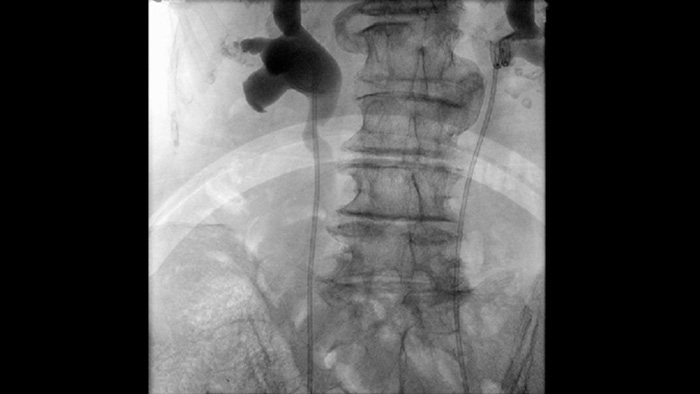

Visualize small devices and vessels with exceptional contrast and spatial resolution

Compare imaging result for cystoscopy and endoscopy images with the live fluoroscopy

Pulsed Fluoroscopy to image dense anatomy

Pulsed Fluoroscopy enhances imaging of dense and complex anatomy to support you in managing dose. You can select a range of fluoroscopy pulse rates to reduce dose when desired or enhance image quality as needed.

Default anatomical settings for urology and endoscopy procedures

Pre-defined imaging parameters for different procedures and anatomy, which can be customized per application, elevate clinical confidence and efficiency for each day’s diverse procedures and patients.